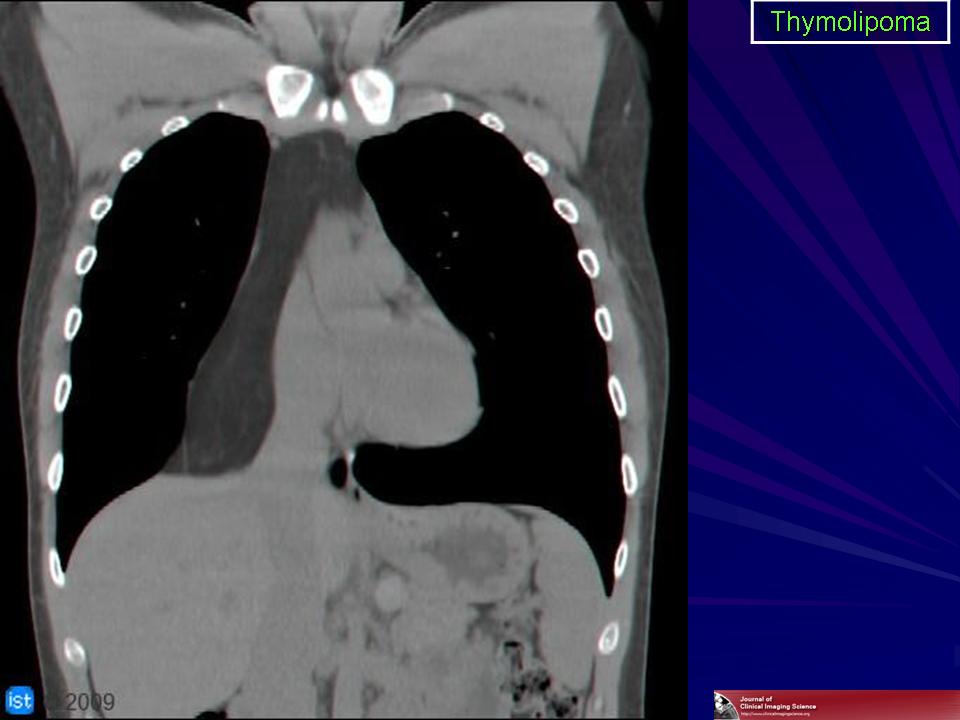

Тимолипома. Как подойти к диагностике? Судя по представленным снимкам, если neo преимущественно жировой структуры локализуется типично для тимомы в переневерхнем средостении + протяженность, объем neo большие и neo выглядит цельным образованием, не составляющими-фрагментами.